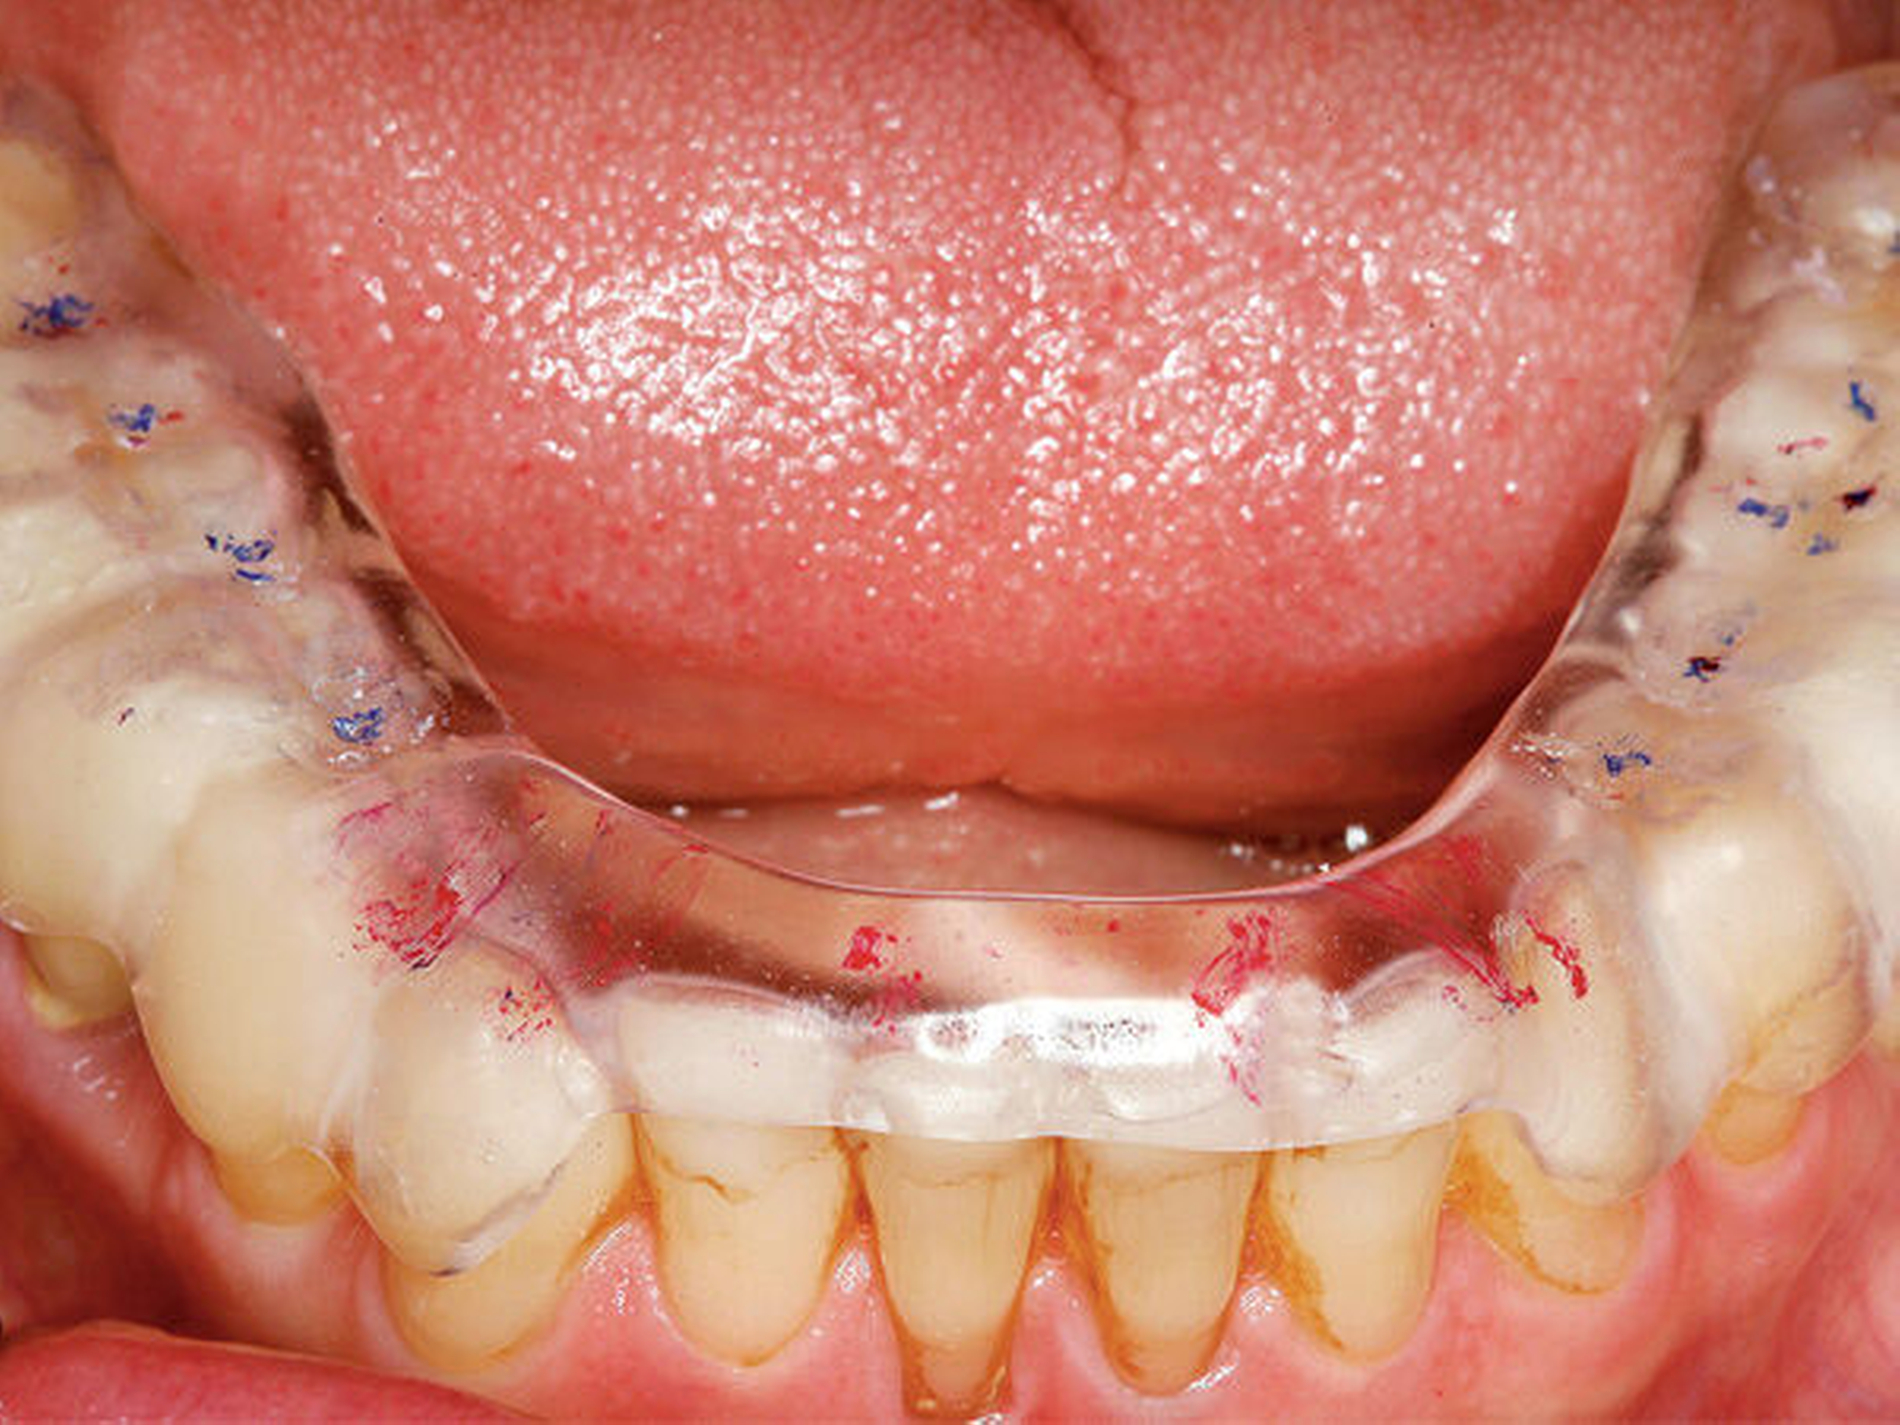

Eingefärbte Schienen können zur Darstellung nächtlicher Bruxismusaktivitäten in Form von Abriebmustern genutzt werden [Ommerborn et al., 2015]. Die Leitlinie weist aber darauf hin, dass damit Schlafbruxismus in Form von Pressen unerkannt bleibt und f ü r Mehrschichtschienen keine ausreichende Evidenz zur Diagnostik von Schlafbruxismus besteht.

Okklusionsschienen gelten als reversible okklusale Ma ß nahmen, die eher symptomatisch eingesetzt den Abrieb der Z ä hne bei Schlafbruxismus verhindern helfen (Abbildung 4). Nachgewiesen werden konnte auch eine Reduktion der Kaumuskelaktivit ä t durch Schienen, dies jedoch nicht regel- und dauerhaft [Guaita et al., 2016; Manfredini et al., 2015]. Vielmehr wird eine intermittierende Trageweise empfohlen, um diesen Effekt auf die Muskulatur zu erzielen [Jokubauskas et al., 2018]. Die Wirkung der Schiene beruht auf einer Veränderung neuromuskulärer Reflexe und einer veränderten Rekrutierung von Muskelfasern durch die veränderte Okklusion [Ispirgil et al., 2018]. Treten jedoch Gewöhnungseffekte auf, verliert sich dieser Effekt.